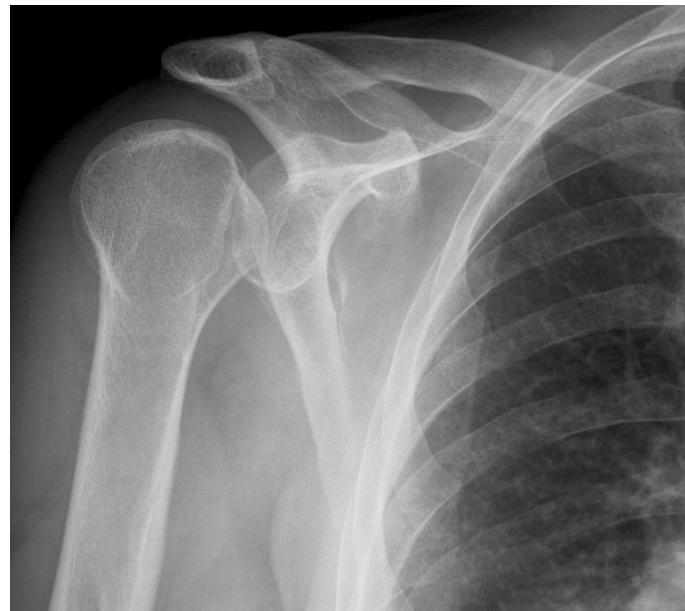

| Feel | • Temperature: Compare both sides (proximal to distal) and comment if symmetrical. • Tenderness: Palpate for tenderness (always compare to the left shoulder) starting at: • Sterno-clavicular (SC) joint • Clavicle • Acromio-clavicular (AC) joint • Greater Tuberosity (GT) & Biceps tendon • Scapular spine • Palpate and compare rotator cuffs (supraspinatus, infraspinatus) and deltoids. General: Tenderness (Generalized/specific), Temperature (compare distal/proximal, Rt/Lt). Anatomic: Skin, Subcut., Muscle (tone, bulk, twitches, gaps, tenderness), Bone (tenderness, mass, crepitus, landmarks: Sternoclavicular, Acromioclavicular, Coracoid Process, Greater Tuberosity, scapular spine, and scapula), Joint (swelling, effusion, crepitation, synovial thickening, joint line tenderness). Specific areas: Acromio-clavicular Jt., Bicipital groove. | ![]() |

| Move | • Ask the patient to stand up. • Active ROM: First Assess range of motion - screen for pain. Ask to perform: • Forward flexion / Extension • Abduction / Adduction • External / Internal rotation • Comment on the motion (e.g., “full active motion, no need for passive”). • Passive ROM: If active motion is limited, assess passively. • Examine joints above and below (e.g., C-spine, elbow). Movement Directions (normal range): Abduction (150°), Forward flexion (180°), Extension (45°), External Rotation (90°), Internal rotation (90°). Flexion / Extension: Look at range, smoothness, painful motion. Abduction / Adduction: Shoulder joint motion is associated with Scapulo-thoracic motion. The first 20°-30° of abduction should not require scapulo-thoracic motion. Note the arc of painful movement (Painful Arc: Supraspinatus, Rotator cuff, Acromio-clavicular). Internal / External Rotation: Apley’s Scratch Test. | ![]() |

| Special Tests | Rotator Cuff Power (compare both sides): • Instability (Bankart): Apprehension Test (abduct and externally rotate arm, apply anterior pressure, watch patient’s face). • Supraspinatus (Empty Can Test): Flex shoulder to 30° with thumbs down; ask patient to resist. • Impingement tests: Neer’s Impingement Test, Hawkins’ Impingement Test. or neer’s rotator cuff + abduction resistance for supraspinatus • Infraspinatus: Ask patient to perform external rotation against resistance (elbows at 90°). • Subscapularis: Ask patient to perform internal rotation against resistance OR use the Lift-Off Test. • Teres Minor: Ask patient to perform external rotation against resistance in 90° of shoulder abduction. • Biceps Tendon: Speed’s Test (resisted shoulder flexion with elbow extended and supinated) OR Yergason Test. • Deltoid: Axillary nerve assessment: Motor (active abduction - then drop test- Deltoid), Sensory (upper lateral aspect of arm). Serratus Anterior - Scapular Winging; long thoracic nerve: push against wall - observe back • AC Joint: Cross Body Adduction Test. • Muscle power tests: Abductors/Adductors, Internal/External Rotators, Serratus Anterior (winging), Biceps Brachii. | Apprehension test: Neer’s Impingement Test: Yergason Test: External / Internal Rotators Strength Test: Supraspinatus Test: Serratus Anterior - Scapular Winging; long thoracic nerve: Biceps Tendon & Ruptured long head: ![]() |

Section 3: Shoulder Pathology & Examination

Questions 17-20: Shoulder Injuries and Tests

Clinical Scenario: 45 years old male fell from height and landed on his shoulder and presented to your clinic with painful shoulder.